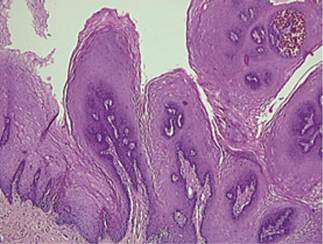

On histological examination finger like papillary projections emerging from a broader stalk consisting of stratified squamous parakeratinized epithelium of variable thickness with acanthosis and thin connective tissue core containing few blood vessels was noted. The epithelium showed basilar hyperplasia. Mild chronic inflammatory infiltration was evident in sub epithelial connective tissue. Correlating with clinical and histological findings, the final diagnosis was given as squamous papilloma of the right lateral border of the tongue.

Figure 4 : H & E stained section at 4X showing papillary projection arising from broader stalk with variable thickness.

Figure 5 : H & E stained section at 10X showing papillary projection arising from broader stalk with variable thickness.